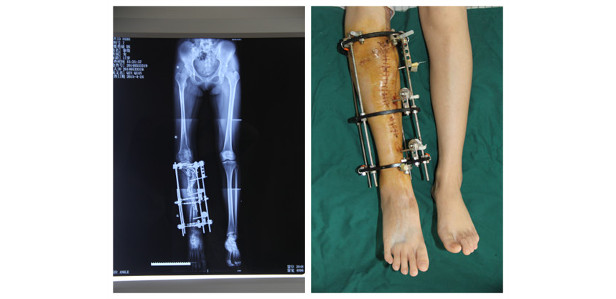

Благодаря всестороннему подходу, направленному на восстановление всей кости целиком, хирургам удалось выпрямить поврежденную ногу Сяоцянь. В ходе операции ее ногу буквально разрезали в форме буквы S, а затем прикрепили к ней винты и специальные пластины. Операция длилась три часа, и в результате все заинтересованные стороны остались довольны.

«Нам удалось выпрямить сильно деформированную ногу Сяоцянь с помощью остеотомии, – рассказывает профессор Тан Цю. – После реабилитации и полного восстановления она, наконец, сможет нормально ходить».